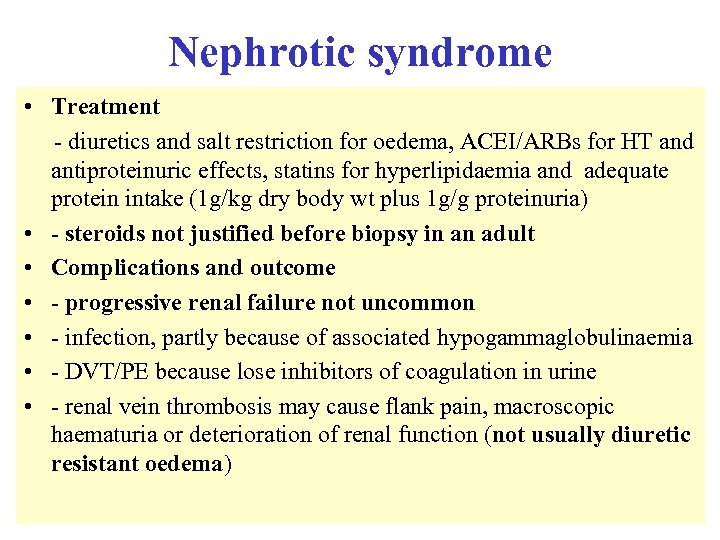

Nephrotic syndrome • Treatment - diuretics and salt restriction for oedema, ACEI/ARBs for HT and antiproteinuric effects, statins for hyperlipidaemia and adequate protein intake (1 g/kg dry body wt plus 1 g/g proteinuria) • - steroids not justified before biopsy in an adult • Complications and outcome • - progressive renal failure not uncommon • - infection, partly because of associated hypogammaglobulinaemia • - DVT/PE because lose inhibitors of coagulation in urine • - renal vein thrombosis may cause flank pain, macroscopic haematuria or deterioration of renal function (not usually diuretic resistant oedema)

Nephrotic syndrome • Treatment - diuretics and salt restriction for oedema, ACEI/ARBs for HT and antiproteinuric effects, statins for hyperlipidaemia and adequate protein intake (1 g/kg dry body wt plus 1 g/g proteinuria) • - steroids not justified before biopsy in an adult • Complications and outcome • - progressive renal failure not uncommon • - infection, partly because of associated hypogammaglobulinaemia • - DVT/PE because lose inhibitors of coagulation in urine • - renal vein thrombosis may cause flank pain, macroscopic haematuria or deterioration of renal function (not usually diuretic resistant oedema)